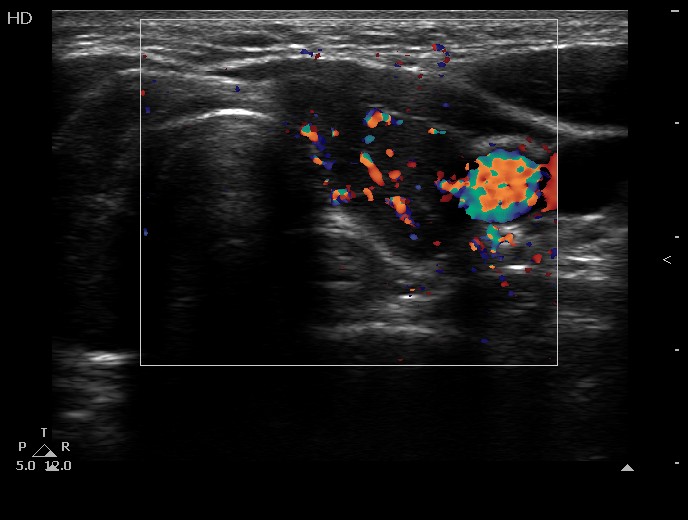

Left lobe, transverse scan, color Doppler mode. The vascularization is increased.